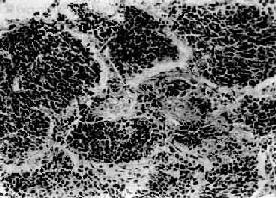

图9-13 全腺泡型肺气肿

末梢呼吸道弥漫性扩张,呈小囊状遍布于肺小叶内(径>200μm)